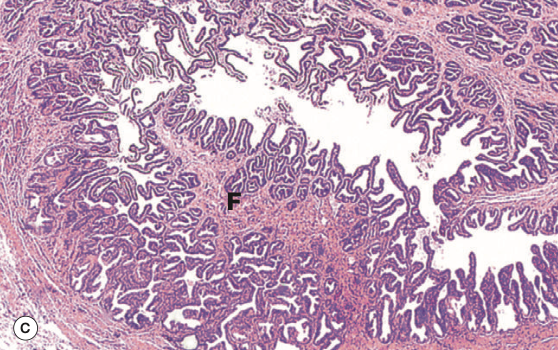

Identify the Organ and Structures?

Gallbladder; can see finger like Villi w/ holes, also see simple columnar epit below MV

Gallbladder; can see finger like Villi but holes not rlly seen?